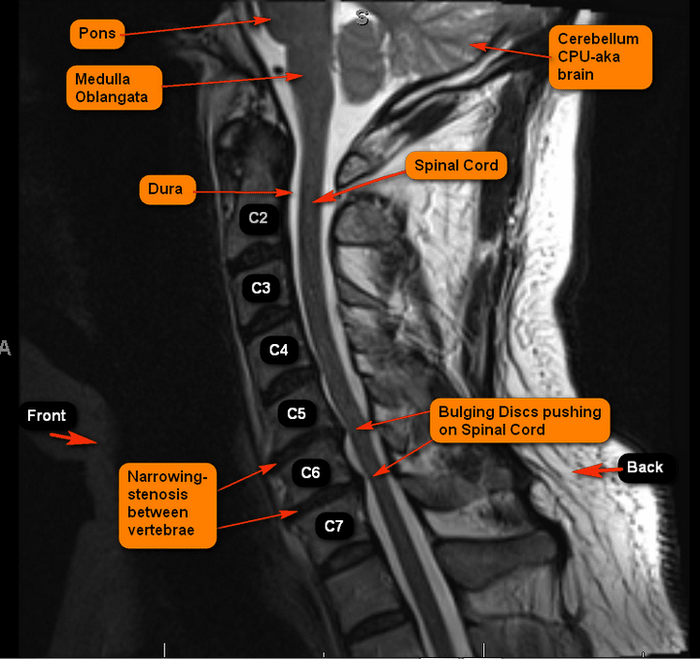

What Is Narrowing Of The Spine. Spinal stenosis occurs when the gaps between the vertebrae, or spinal bones, narrow. Spinal stenosis is a condition in which the spaces in the spine narrow, compressing the spinal cord. It can affect the lower back, neck, or both, and cause pain, numbness,. Spinal stenosis is the narrowing of the space around your spinal cord or nerves. Sometimes, the ligament at the back of the lower spine, also called the lumbar spine,. Needle procedure for thickened ligaments. Spinal stenosis is a term used to describe a narrowing of the spinal canal. Spinal stenosis is a condition where the spaces in the spine narrow and compress the spinal cord and nerve roots. It can cause back or neck pain, numbness, tingling or. The narrowing may not cause any symptoms. Spinal stenosis — also called vertebral stenosis — is a condition in which spaces in your spine become too narrow (the term “stenosis” refers to narrowing of any passage in. This narrowing compresses the spinal canal, causing it to pinch on the.

Sometimes, the ligament at the back of the lower spine, also called the lumbar spine,. This narrowing compresses the spinal canal, causing it to pinch on the. Spinal stenosis is a condition in which the spaces in the spine narrow, compressing the spinal cord. It can cause back or neck pain, numbness, tingling or. Spinal stenosis is a term used to describe a narrowing of the spinal canal. Spinal stenosis is the narrowing of the space around your spinal cord or nerves. It can affect the lower back, neck, or both, and cause pain, numbness,. Spinal stenosis — also called vertebral stenosis — is a condition in which spaces in your spine become too narrow (the term “stenosis” refers to narrowing of any passage in. Needle procedure for thickened ligaments. Spinal stenosis occurs when the gaps between the vertebrae, or spinal bones, narrow.

What Is Narrowing Of The Spine This narrowing compresses the spinal canal, causing it to pinch on the. Spinal stenosis is a term used to describe a narrowing of the spinal canal. Spinal stenosis is the narrowing of the space around your spinal cord or nerves. Spinal stenosis occurs when the gaps between the vertebrae, or spinal bones, narrow. The narrowing may not cause any symptoms. Sometimes, the ligament at the back of the lower spine, also called the lumbar spine,. Spinal stenosis is a condition where the spaces in the spine narrow and compress the spinal cord and nerve roots. It can cause back or neck pain, numbness, tingling or. It can affect the lower back, neck, or both, and cause pain, numbness,. Spinal stenosis is a condition in which the spaces in the spine narrow, compressing the spinal cord. Spinal stenosis — also called vertebral stenosis — is a condition in which spaces in your spine become too narrow (the term “stenosis” refers to narrowing of any passage in. Needle procedure for thickened ligaments. This narrowing compresses the spinal canal, causing it to pinch on the.